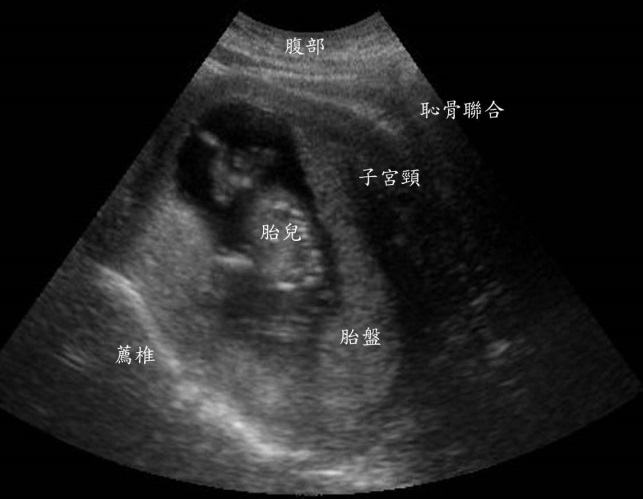

我需要高層次超音波檢查嗎?